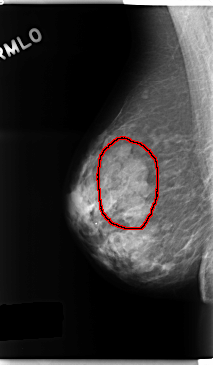

FILE: C_0247_1.RIGHT_MLO.OVERLAY

TOTAL_ABNORMALITIES 1

ABNORMALITY 1

LESION_TYPE MASS SHAPE LOBULATED MARGINS CIRCUMSCRIBED

ASSESSMENT 3

SUBTLETY 4

PATHOLOGY BENIGN

TOTAL_OUTLINES 1

BOUNDARY